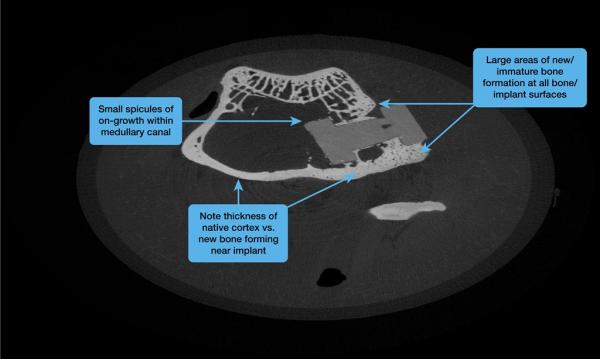

ジョージア州アルファレッタ、2017年11月10日 - 特殊ポリマーの世界的サプライヤーであるソルベイは、医療機器メーカーのDiFusion Technologies社が、脊椎インプラント用のZFUZE骨伝導性PEEK複合材のベースポリマーとして、Zeniva(r) ZA-500ポリエーテルエーテルケトン(PEEK)を採用したことを本日発表しました。DiFusion社による最新の試験では、この新しい複合材により、骨インプラント表面全体で広範囲にわたる新たな骨形成が見られました。この結果は、このほどオーランドで開催されたNASS 2017イベントで発表されました。

PEEKは、弾性が骨に類似し、またその放射線透過性によってX線による可視化も容易であることから、脊椎インプラントにおいてチタニウムの有力な代替となり得ます。またPEEKは不活性であり、人体組織との反応を引き起こしません。この特性が生体適合性を示す一方、PEEKそのものが骨の成長を促進することもありません。DiFusion社は、マイナスに電荷を帯びたゼオライトをソルベイのZeniva(r) PEEKにコンパウンドすることで、この問題を解決しました。